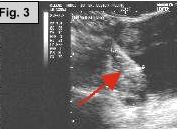

Fig. 1a-c: MRI of the L-spine (sagittal T2 weighted, coronal scout, and coronal MR Myelogram, respectively) demonstrates an incidental 4-5 cm cystic-appearing mass in the right pelvis on limited views of the pelvis. Fig. 2: a helical CT image of the pelvis, revealing a 4x5 cm low-density mass in the right hemipelvis to the right of the uterus. Fig. 3: Pelvic ultrasound shows a moderately enlarged right adnexa measuring 5 cm with low-level echoes.

IMAGING FINDINGS:  Fig. 1a-c show MRI images of the L-spine (sagittal T2 weighted, coronal scout, and coronal MR Myelogram, respectively).  They demonstrate mild scattered disc bulges and an incidental 4-5 cm cystic-appearing mass in the right pelvis on limited views of the pelvis. Incidentally, the MR Myelogram (Fig. 1c) also nicely shows the thecal sac and renal collecting systems.  Fig. 2 shows a helical CT image of the pelvis, revealing a 4x5 cm low-density mass in the right hemipelvis to the right of the uterus with CT density of about 20 Hounsfield units on pre- and post-contrast images.  A repeat transabdominal and endovaginal pelvic ultrasound with Doppler performed at AIC (Fig. 3) showed a moderately enlarged right adnexa measuring 5 cm with low-level echoes.